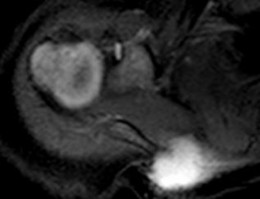

A 15-year-old male presents with deep knee pain awakening him at night. Radiographs show a permeative destructive lesion in the distal femoral metaphysis with a 'sunburst' periosteal reaction and Codman's triangle.

Biopsy confirms high-grade conventional osteosarcoma. What is the most critical prognostic factor for long-term overall survival in this patient?

Explanation

For localized high-grade osteosarcoma, the most important prognostic indicator is the histologic response to neoadjuvant chemotherapy. This is evaluated during the definitive resection. A 'good response' is typically defined as greater than 90% or 99% tumor necrosis. Patients who achieve this level of necrosis have a significantly improved disease-free and overall survival rate compared to 'poor responders' who have extensive viable tumor cells remaining.